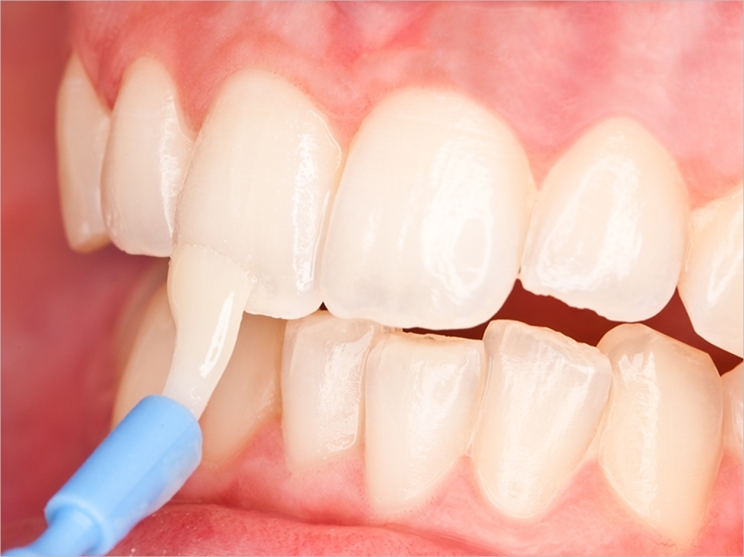

Fluoride applications are a safe and effective way to safeguard your growing child's teeth from developing decay. The fluoride is painted onto the surface of the child's teeth and this helps to mineralise the teeth.